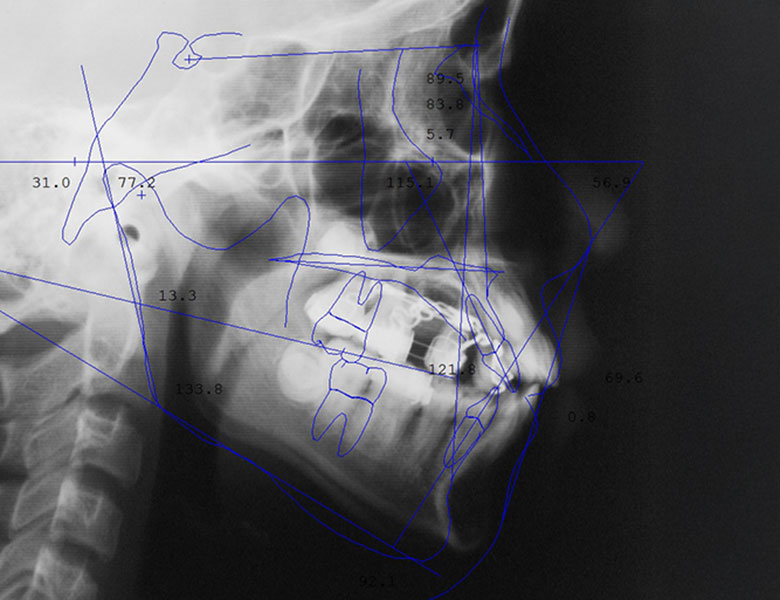

矯正歯科治療

五反田の歯医者、ツツミ歯科クリニックの矯正歯科治療

iTeroによる3Dシミュレーション

見えない・目立たない選択肢も

口腔内スキャナー「iTero(アイテロ)」を導入し、矯正治療前に歯並びの変化を3Dシミュレーションでご確認いただけます。

見た目や期間、ライフスタイルに配慮しながら、無理のない治療計画をご提案。

裏側(舌側)矯正、インビザライン、部分矯正、マイオブレイスなど、幅広い矯正治療をご用意しています。